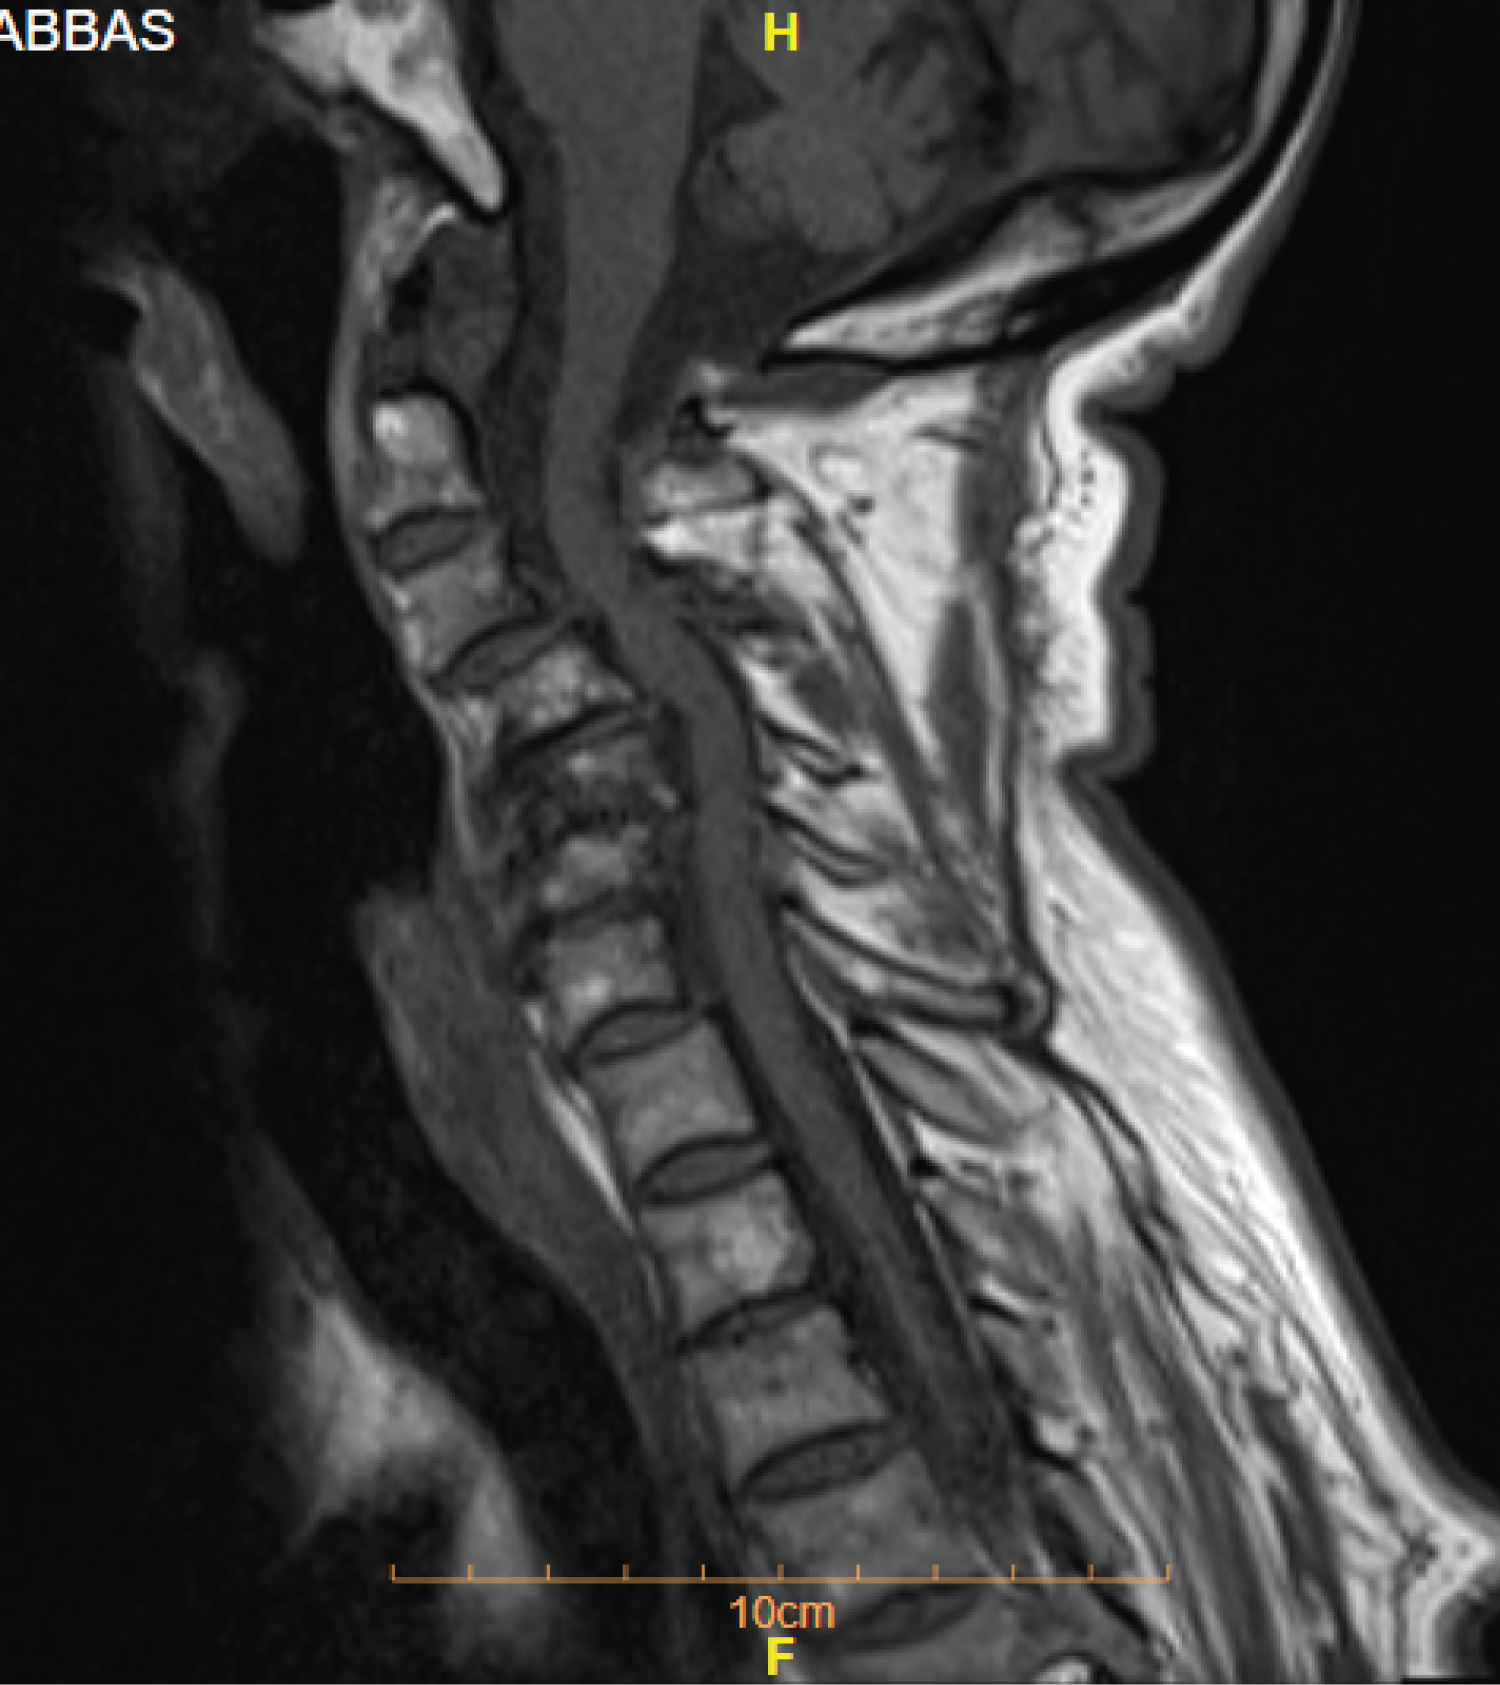

Magnetic Resonance Imaging (MRI) of the cervical spine showed stenosis with cord compression from C3 to C7 levels (Figure 1). Sagittal computed tomography image of the cervical spine showing ossified yellow ligament from c4 to c7 (Figure 2 and Figure 3).

Figure 1: Sagittal T1 weighted MR image of the cervical spine showing a narrowed spinal canal due to a low signal intensity mass anterior to the posterior elements with cord oedema at C4 - C7 levels. View Figure 1